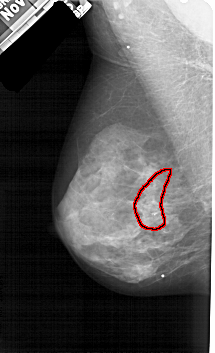

A_1605_1.RIGHT_MLO

FILE: A_1605_1.RIGHT_MLO.OVERLAY

TOTAL_ABNORMALITIES 1

ABNORMALITY 1

LESION_TYPE CALCIFICATION TYPE PLEOMORPHIC DISTRIBUTION SEGMENTAL

ASSESSMENT 4

SUBTLETY 3

PATHOLOGY BENIGN

TOTAL_OUTLINES 1

BOUNDARY